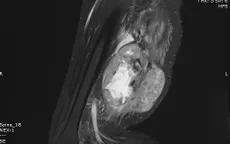

Cắt bỏ khối sarcoma sụn ác tính hiếm gặp, bảo toàn chi cho bệnh nhân

VTV.vn - Bệnh viện Bãi Cháy (Quảng Ninh) vừa phẫu thuật lấy toàn bộ khối sarcoma sụn ác tính hiếm gặp, giúp bệnh nhân thoát nguy cơ cắt cụt chi.